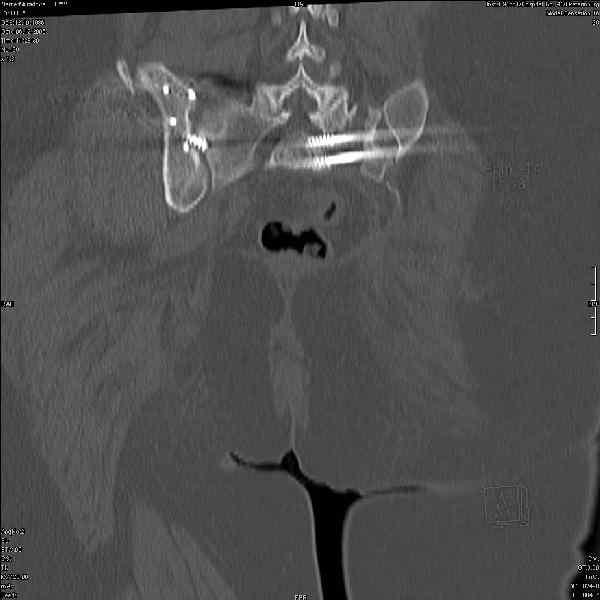

Здравствуйте, коллеги. Какие будут мнения по поводу лечения представляемой больной?

Молодая девушка 19 лет, травма 1 год назад, тогда же прооперирована.

В настоящее время имеются ноющие боли в области крестца слева, нарушение походки, ощущение неуверенности, слабости в левой нижней конечности, неврологически -непостоянные парестезии в левой нижней конечности. Ходит с дополнительной опорой, страдает от ожирения.

Какова по вашему будет оптимальная тактика в отношении несращения крестца? Замена винтов на более длинные с коррекцией их положения+ туннелизация зоны нестращения, открытое вмешательство с костной аутопластикой или еще какие варианты?

В приложении снимки при поступлении и послеоперационные год назад.

Могу сказать одно: миграция винтов и нестабильность синтеза левого подвздошно-крестцовогоо сочленения очевидна.

были использованы винты 7.2 мм, кроме того иетодика транссакральной фиксации не является общепринятой и широко рекомендуемой, но и в этих случаях они наблюдали случаи вторичного смещения